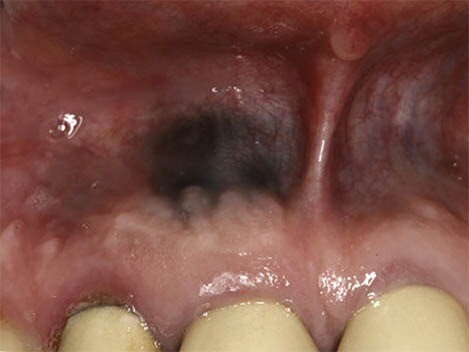

What Causes a Black Spot on Your Gums?

First, we recommend taking a moment to breathe and relax. According to the Oral Cancer Foundation, dark spots rarely indicate a serious condition like cancer and are usually benign. Spots in the mouth are often not fully black but may appear that way as they can be hard to see. We’re here to help walk you through the causes of dark spots in your mouth and what they mean.

Causes of Dark Spots on Gums

Oral conditions like dark spots on your gums have various causes and can be challenging to diagnose. These spots can either be harmless or the result of an underlying disease, so it's essential to speak to your doctor if you believe you have any symptoms.

What exactly causes black spots on your gums? There are two categories of answers: those with internal causes and those with external causes.

Internal pigments that cause skin colour changes can also modify your gums' colour to black, grey, blue, or brown. Blood vessels can even dysfunction or rupture, leading to discolouration.

Melanin can be altered by a variety of diseases and disorders that affect the production of this pigment. Cells in your body that produce melanin are called melanocytes.

Tuberculosis and Addison's disease can affect your adrenal glands and cause changes in pigmentation.

HIV, also called the human immunodeficiency virus, can lead to pigmented lesions in the mouth.

According to a research article published in the Journal of Indian Academy of Oral Medicine and Radiology, haemangiomas are most common soft tissue benign tumours, composed of blood vessels, and occur in the head and neck region (60%) and less commonly in the oral cavity; oral cavity if affected involves gingiva followed by the lips, tongue and palate.

External Causes

Exposure of your mouth to pigment produced outside the body can lead to discolouration in the form of dark or spots on the gums. Sources outside the body can also affect your body's production or regulation of pigment or iron, leading to a change in colour. These black dots can be caused by:

Oral Cancer

In rare cases, benign lesions that don't require treatment may transform into oral malignant melanoma, a type of oral cancer. A doctor will look at a range of factors to see if the lesion qualifies as melanoma. According to a research article published in the Journal of Indian Academy of Oral Medicine and Radiology, melanoma constitutes only 3–5% of all cutaneous malignancies, and oral melanoma is an aggressive neoplasm which accounts for less than 0.5%.

If you believe you have oral cancer symptoms, we recommend leaving the diagnosis up to the professionals and speaking to your doctor. If you exhibit symptoms, they may perform a biopsy (laboratory tests of your tissue) to confirm melanoma.

Remember that cancer is a rare cause of any dark spots in your mouth. A more benign explanation is much more likely, so don't stress. You've done a great job informing yourself of the possible causes, so be sure to make the next step for success and schedule an appointment or regular check-ups with your doctor.